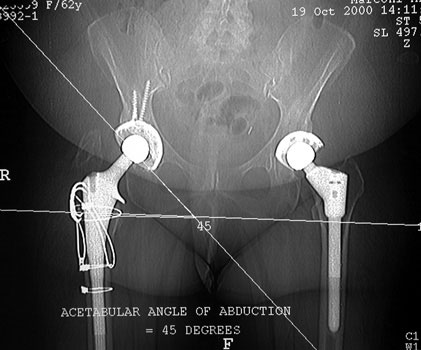

Acetabular component lateral inclination

• Transischial line obtained on pilot image

• Line drawn through cup

ACETABULAR COMPONENT

CT Measurements